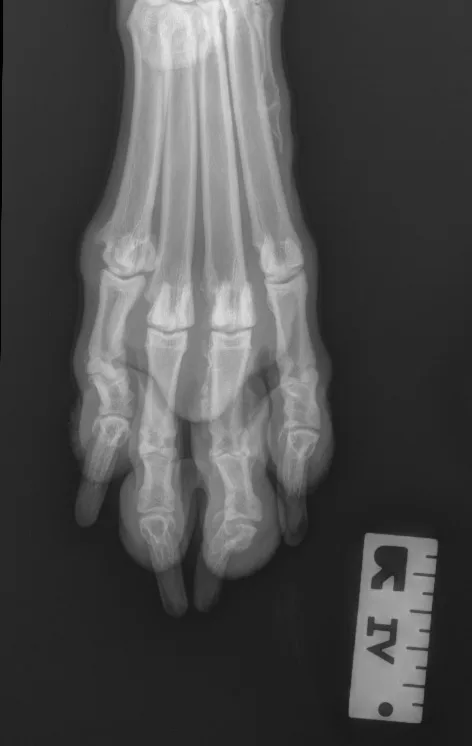

Step-by-Step: Positioning a Pelvic Limb for a Dorsal/Palmar View of the Digits

What You Will Need

V-trough sponge positioner

Wooden spoon (optional)

Tape

Gauze

Step 1: Position the Patient

Place the patient in dorsal recumbency. Center the abdomen over a V-trough sponge positioner to keep the body straight; ensure the pelvis and caudal abdomen are outside of the trough. Make sure both pelvic limbs are completely extended and the unaffected limb is not in the imaging view.

Author Insight

To evaluate the entire bony structures, the digits may need to be separated manually (using either a wooden spoon to press down and spread the digits or using gauze without woven radiopaque detectors) and taped down.

Step 2: Position the Beam

Center the collimator beam over the tarsometatarsal joints to include the distal metatarsals and all digits (the tarsus can also be included).

All digits should be separated and clearly visible. The bony edges of the metacarpal bones should be parallel to each other (arrows), and all phalanges (P1 [A], P2 [B], P3 and nail [C]) should be included.